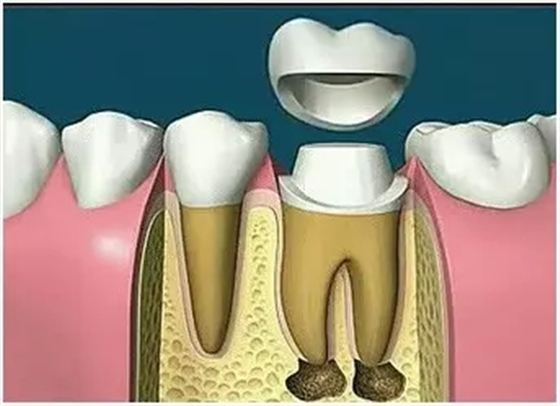

7、根管打樁

因牙體缺損過多,導(dǎo)致牙的強(qiáng)度(承受力量的性能)大幅度下降,不能很好地承受咀嚼力量。打樁的目的是增加牙根及牙冠的強(qiáng)度,增加患牙的穩(wěn)固。

8、完成牙體修復(fù)

X線片顯示根管充填完好,行暫時(shí)或永久牙體修復(fù),帶上牙冠,保護(hù)患牙。至此根管治療才可算完成,同時(shí)根管治療后還需復(fù)診,一般周期可為3個(gè)月、半年、1年、2年或更長。